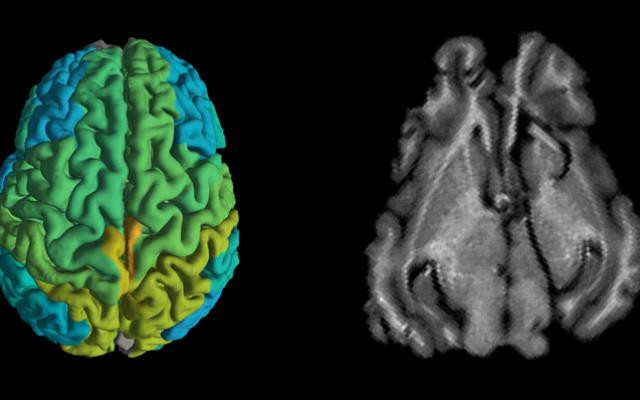

Kỹ thuật MRI mới giúp sớm phát hiện các căn bệnh thoái hóa thần kinh ảnh 1(Nguồn: timesofisrael.com)

Theo công trình nghiên cứu được đăng trên tạp chí Nature Communications ngày 30/7, các nhà khoa học thuộc Đại học Hebrew ở Jerusalem cho biết đã phát triển một mô hình toán học có thể thu thập được thông tin về những thay đổi phân tử trong não bộ từ hình ảnh MRI.